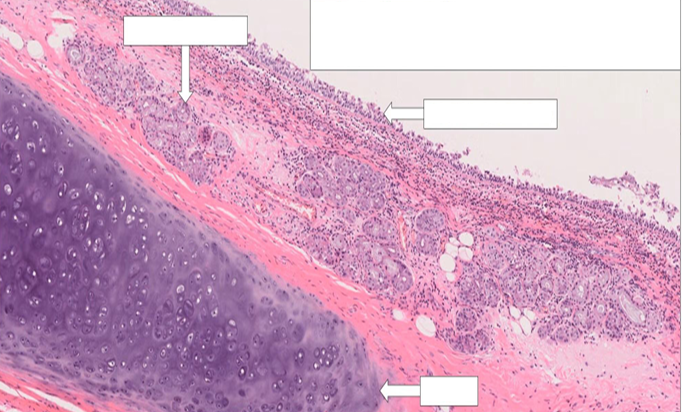

Trachea

(medium power view)

upper part: submucosa

lower part: cartilage